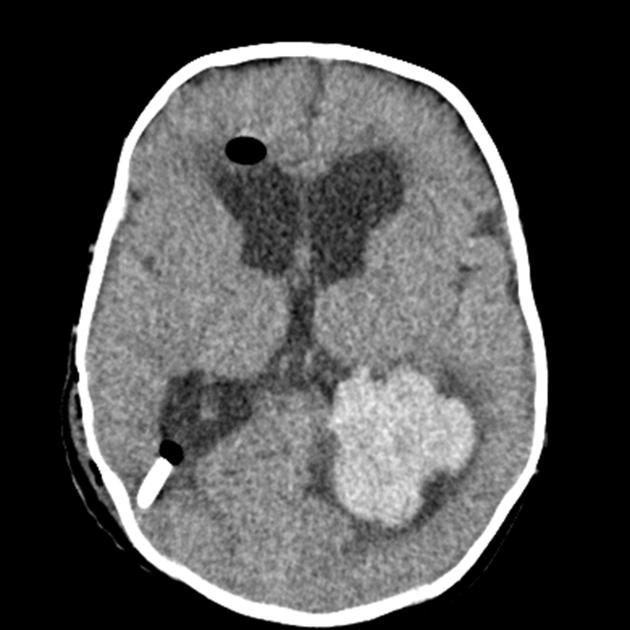

Ung thư biểu mô đám rối màng mạch bắt đầu gần mô não tiết ra dịch não tủy. Một khối u không phải ung thư của khu vực này được gọi là u nhú đám rối màng mạch (choroid plexus papilloma). Khi khối u to lên, nó sẽ ảnh hưởng đến chức năng của các cấu trúc lân cận trong não, gây ra tình trạng dư thừa chất lỏng trong não (não úng thủy), khó chịu, buồn nôn hoặc nôn và đau đầu.

- Kiểm tra não bằng hình ảnh. Các xét nghiệm để tạo ra hình ảnh về não của bạn có thể bao gồm chụp cộng hưởng từ (MRI) và chụp cắt lớp vi tính (CT). Chụp cộng hưởng từ cũng giúp bác sĩ lập kế hoạch phẫu thuật.